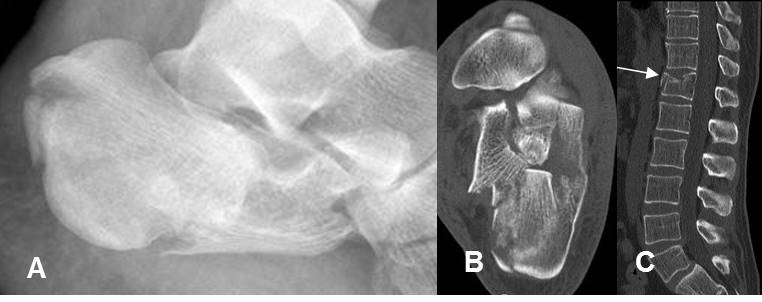

Fig 202. Fractura del paleador.

A: Rx lateral. No se aprecian alteraciones, pero solo son evaluables 5 cuerpos vertebrales.

B: TAC axial C: TAC reconstrucción sagital. Fracturas no desplazadas en las apófisis espinosas de C6 y C7.